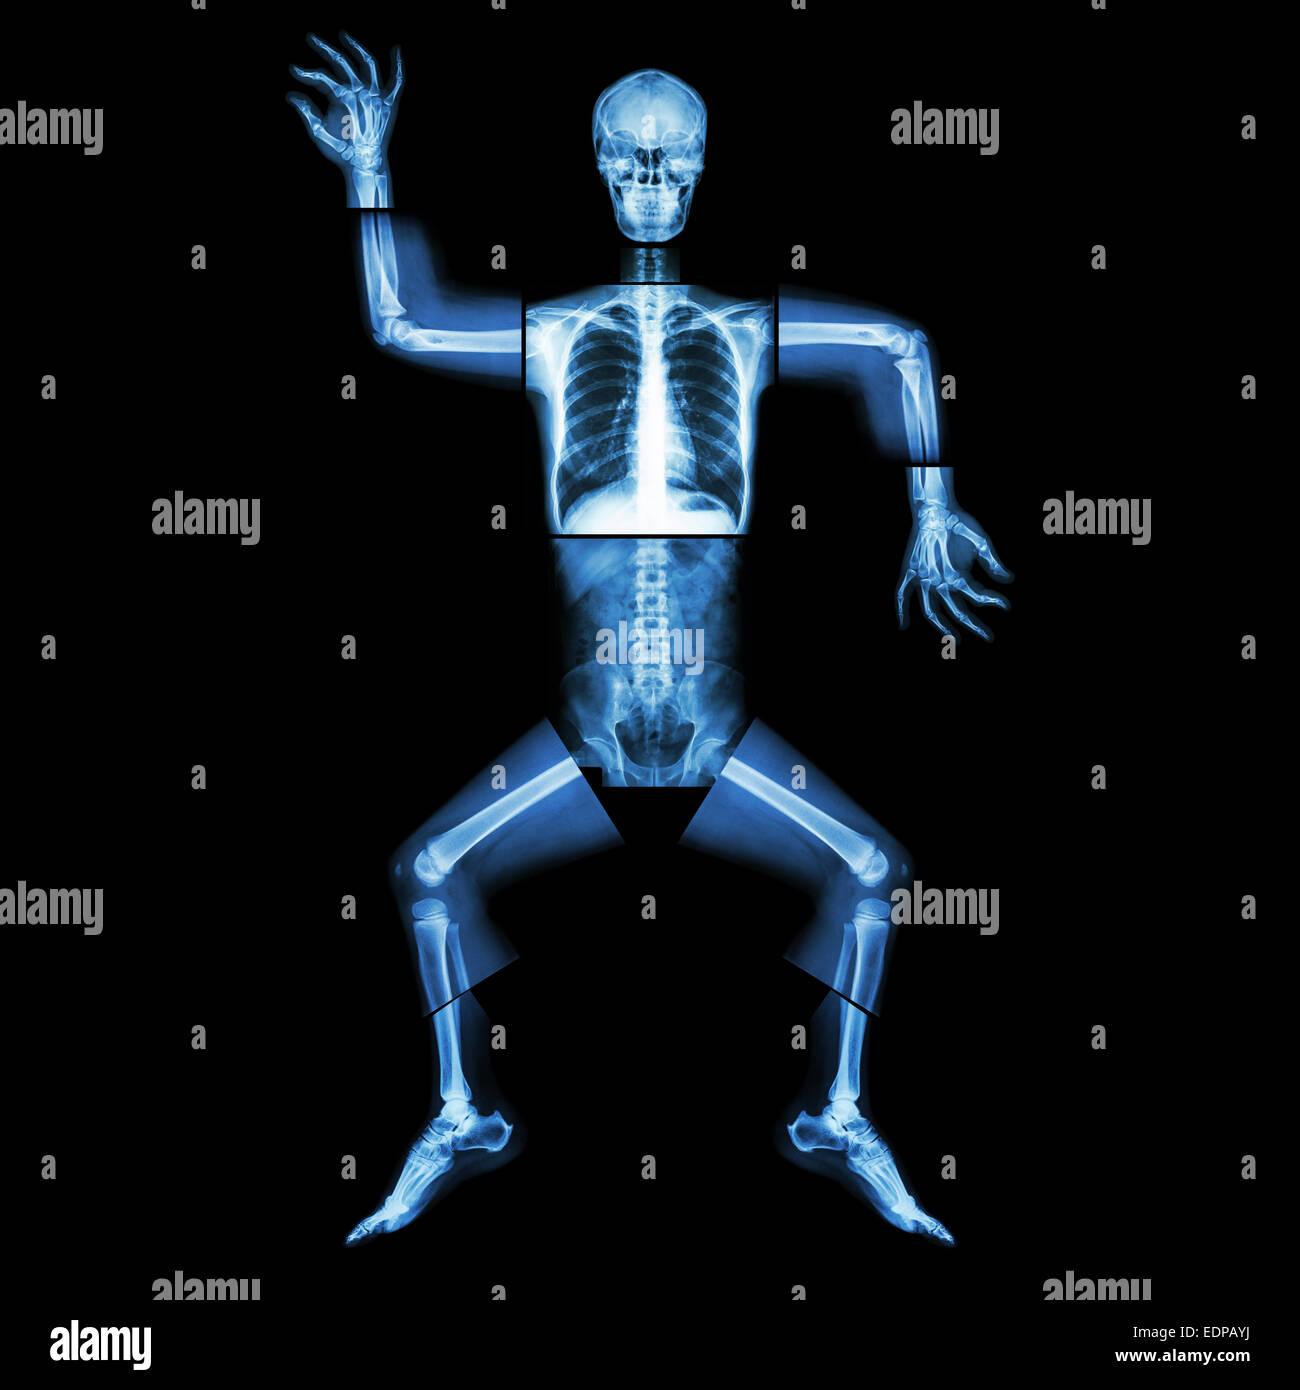

La danse aérobie(os humains est la danse),(corps entier x-ray : tête, cou, thorax, bras, épaule, coude, avant-bras, main, doigt joint , Banque D'Imageshttps://www.alamyimages.fr/image-license-details/?v=1https://www.alamyimages.fr/photo-image-la-danse-aerobie-os-humains-est-la-danse-corps-entier-x-ray-tete-cou-thorax-bras-epaule-coude-avant-bras-main-doigt-joint-77323560.html

La danse aérobie(os humains est la danse),(corps entier x-ray : tête, cou, thorax, bras, épaule, coude, avant-bras, main, doigt joint , Banque D'Imageshttps://www.alamyimages.fr/image-license-details/?v=1https://www.alamyimages.fr/photo-image-la-danse-aerobie-os-humains-est-la-danse-corps-entier-x-ray-tete-cou-thorax-bras-epaule-coude-avant-bras-main-doigt-joint-77323560.htmlRFEDPAYM–La danse aérobie(os humains est la danse),(corps entier x-ray : tête, cou, thorax, bras, épaule, coude, avant-bras, main, doigt joint ,

La danse aérobie(os humains est la danse),(corps entier x-ray : tête, cou, thorax, bras, épaule, coude, avant-bras, main, doigt joint , Banque D'Imageshttps://www.alamyimages.fr/image-license-details/?v=1https://www.alamyimages.fr/photo-image-la-danse-aerobie-os-humains-est-la-danse-corps-entier-x-ray-tete-cou-thorax-bras-epaule-coude-avant-bras-main-doigt-joint-77323562.html

La danse aérobie(os humains est la danse),(corps entier x-ray : tête, cou, thorax, bras, épaule, coude, avant-bras, main, doigt joint , Banque D'Imageshttps://www.alamyimages.fr/image-license-details/?v=1https://www.alamyimages.fr/photo-image-la-danse-aerobie-os-humains-est-la-danse-corps-entier-x-ray-tete-cou-thorax-bras-epaule-coude-avant-bras-main-doigt-joint-77323562.htmlRFEDPAYP–La danse aérobie(os humains est la danse),(corps entier x-ray : tête, cou, thorax, bras, épaule, coude, avant-bras, main, doigt joint ,

La danse aérobie(os humains est la danse),(corps entier x-ray : tête, cou, thorax, bras, épaule, coude, avant-bras, main, doigt joint , Banque D'Imageshttps://www.alamyimages.fr/image-license-details/?v=1https://www.alamyimages.fr/photo-image-la-danse-aerobie-os-humains-est-la-danse-corps-entier-x-ray-tete-cou-thorax-bras-epaule-coude-avant-bras-main-doigt-joint-77323565.html

La danse aérobie(os humains est la danse),(corps entier x-ray : tête, cou, thorax, bras, épaule, coude, avant-bras, main, doigt joint , Banque D'Imageshttps://www.alamyimages.fr/image-license-details/?v=1https://www.alamyimages.fr/photo-image-la-danse-aerobie-os-humains-est-la-danse-corps-entier-x-ray-tete-cou-thorax-bras-epaule-coude-avant-bras-main-doigt-joint-77323565.htmlRFEDPAYW–La danse aérobie(os humains est la danse),(corps entier x-ray : tête, cou, thorax, bras, épaule, coude, avant-bras, main, doigt joint ,

La danse aérobie(os humains est la danse),(corps entier x-ray : tête, cou, thorax, bras, épaule, coude, avant-bras, main, doigt joint , Banque D'Imageshttps://www.alamyimages.fr/image-license-details/?v=1https://www.alamyimages.fr/photo-image-la-danse-aerobie-os-humains-est-la-danse-corps-entier-x-ray-tete-cou-thorax-bras-epaule-coude-avant-bras-main-doigt-joint-77323558.html

La danse aérobie(os humains est la danse),(corps entier x-ray : tête, cou, thorax, bras, épaule, coude, avant-bras, main, doigt joint , Banque D'Imageshttps://www.alamyimages.fr/image-license-details/?v=1https://www.alamyimages.fr/photo-image-la-danse-aerobie-os-humains-est-la-danse-corps-entier-x-ray-tete-cou-thorax-bras-epaule-coude-avant-bras-main-doigt-joint-77323558.htmlRFEDPAYJ–La danse aérobie(os humains est la danse),(corps entier x-ray : tête, cou, thorax, bras, épaule, coude, avant-bras, main, doigt joint ,